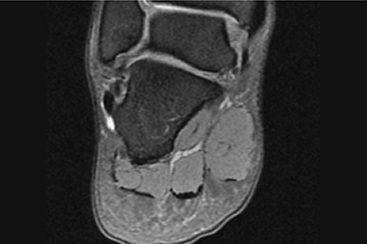

발목 인대 봉합술이란?

관절 내시경을 이용하여 찢어진 인대를 봉합하거나, 손상된 인대를 보강하는 수술입니다.

파열되거나 손상된 인대를 접합하는 수술로 발목 통증이 보존적 치료로 호전되지 않고 지속되거나 반복적으로 발목을 접질릴 경우,

파열이나 변형 정도에 맞는 수술을 시행하여 건강한 인대의 기능을 회복하고 보강하는 치료입니다.

인대봉합술은 파열된 인대를 본래 해부학적 위치해 봉합해주는 수술방법으로 다치기 전과 동일한 기능회복이 가능합니다.

발목인대파열

흔히 발목을 삐었다, 인대가 늘어났다고 말하는 경우 대부분 외측 인대 손상이 많습니다.

인대 손상은 운동에 따라 나누어 인대의 파열이 발생하기도 합니다.

발목 인대가 손상되었을 때 제대로 치료하지 않으면, 방치되거나 회복되지 않으면,

인대는 제 기능을 발휘하지 못하고 발목 관절 불안정성으로 인해 만성 통증이 발생하게 됩니다.

뿐만 아니라 발목 내부에 위치한 뼈가 서로 부딪히게 되고, 연골을 함께 손상시킬 수도 있습니다.

인대파열 MRI

발목 인대가 파열되면 나타나는 증상

• 접질린 발목 부위가 붓고 통증이 생깁니다.

• 발을 디딜 때 불안정함을 느낍니다.

• 심할 경우 다치는 순간 인대가 파열되며 찢어지는 소리가 날 수 있습니다.

• 만성화될 경우 장시간 보행 시 발목 통증이 있고, 양반다리를 하기 어려울 수 있습니다.